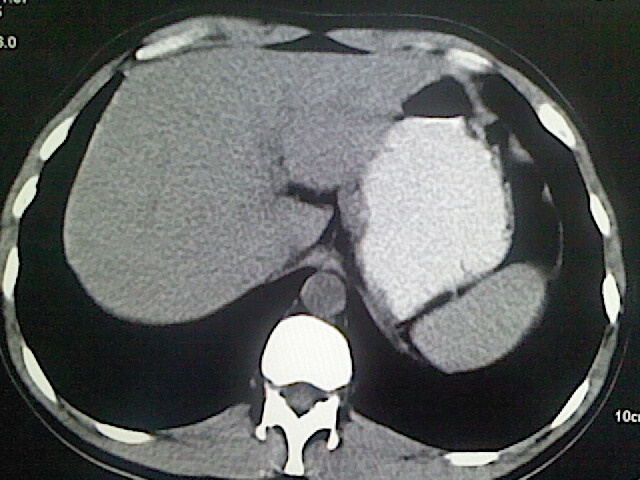

以下是引用卜一在2009-3-14 9:49:00的发言:[br]胆囊萎缩,胆囊壁不规则增厚,内部结构模糊,增强明显强化。另:肝左叶外侧段肝囊肿。支持:慢性胆囊炎!高度可疑:胆囊癌!

以下是引用余辉在2009-3-14 8:48:00的发言:[br]1)慢性胆囊炎。2)肝左叶外侧段肝囊肿。3)脂肪肝。[br]支持,胆囊萎缩,密度增高,不知b超具体有何提示,钙胆汁?结石?

以下是引用jiangjing在2009-3-14 10:18:00的发言:[br]1)慢性胆囊炎。2)肝左叶外侧段肝囊肿。3)脂肪肝。4.】建议行肝功能检查